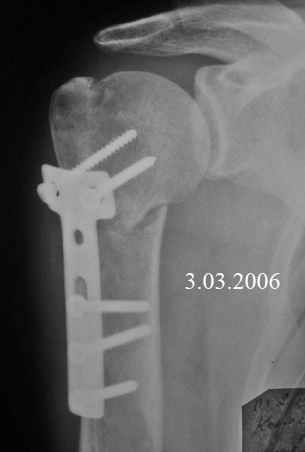

Пациент после автодорожной травмы, оперированным переломо-вывихом плеча.Уважаемые коллеги, помогите разобраться с ситуацией. К нам в больницу обратился пациент 29 лет, проживающий в области. Травма автодорожная 13.01.06. (перевернулся в автомобиле), оперирован в районной больнице 17.01.06 - открытое вправление вывиха и остеосинтез шейки плеча пластиной.Объективно: Выраженная гипотрофия дельтовидной, надлопаточной и подлопаточной мышц. Движения в плечевом суставе резко болезненные, имеется значительное ограничение движений. Активные движения: сгибание до 70гр, отведение 10гр, кзади рука не отводится, пассивные движения: сгибание до 90гр, отведение до20гр ( вместе с лопаткой до 30гр). Сила в кисти сохранена.

Перелом типа А3 по АО. Не очень хорошо отрепонирован. Учитывая, что головка вроде в хорошем состоянии в плане АВН, советовал бы реостеосинтез пластиной с угловой стабильностью. А вот проблемы с суставом очень напоминают повреждение вращательной манжеты. Поэтому сначала есть смысл сделать артропневмографию, выход контраста субакромиально - патогномоничный признак разрыва коротких ротаторов. После этого можно обсудить объем операции.